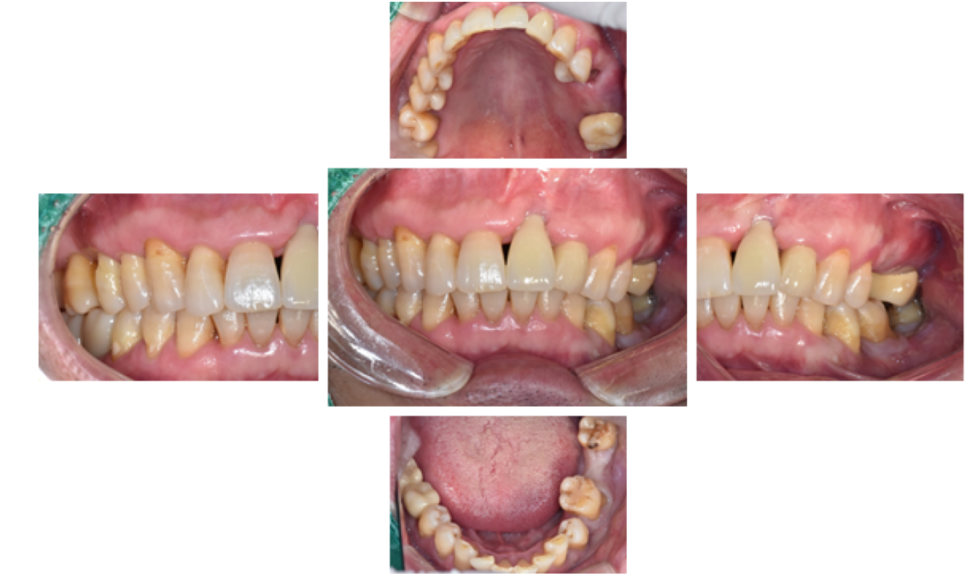

오늘은 앞니가 빠져서 내원 한 50대 남자분의 앞니와 어금니 임플란트와 전체적인 치료 증례를 소개해 드리려고 합니다.

2주 전 집에서 앞니가 빠져서 내원하셨고,

왼쪽 아래 어금니는 부었다가 내원 당일에는 가라앉았다고 하셨어요.

전체적인 치료보다는 일단 앞니 치료를 먼저 원하셨습니다

전체적인 구강 판단을 위해

파노라마 엑스레이 사진을 찍었습니다.

왼쪽 큰앞니도 빠져있지만,

오른쪽위 큰어금니, 오른쪽 아래 큰어금니도 발치된 상태였고,

왼쪽 위 브릿지 상태도 좋지는 않았습니다.

왼쪽 아래 큰어금니 하나는 뿌리만 남은 상태였어요.

그러나 일단 앞니가 눈에 가장 먼저 보이는 부위이고,

환자분이 앞니 치료를 가장 먼저 원하셨기 때문에,

앞니 먼저 진행하기로 하였습니다.

그리고 앞니를 먼저 진행하는 동안, 전체적인 잇몸 관리를 먼저 해드리기로 했습니다.

왼쪽 아래 임플란트 식립 수술 전,

중간확인차 전체 입안 사진 촬영을 하였습니다.

환자분은 오른쪽으로 식사는 잘 하고 계셨고,

왼쪽치료를 진행중인 상태입니다.

왼쪽 앞니의 경우에는,

오랜 염증으로 잇몸과 뼈가 많이 내려간 상태라 보철이 조금 길어지는 한계가 있었습니다...ㅠㅠ